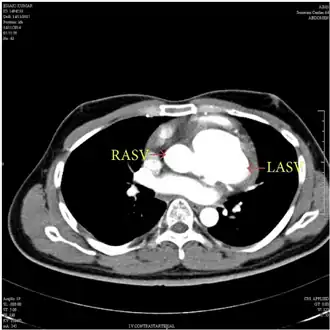

Diagnostic methodEchocardiogram, cardiac CT scan, cardiac MRI scan

Aneurysm of the aortic sinus, also known as the sinus of Valsalva, is a rare abnormality of the aorta, the largest artery in the body. The aorta normally has three small pouches that sit directly above the aortic valve (the sinuses of Valsalva), and an aneurysm of one of these sinuses is a thin-walled swelling. Aneurysms may affect the right (65–85%), non-coronary (10–30%), or rarely the left (< 5%) coronary sinus.[1] These aneurysms may not cause any symptoms but if large can cause shortness of breath, palpitations or blackouts. Aortic sinus aneurysms can burst or rupture into adjacent cardiac chambers, which can lead to heart failure if untreated.

The first step in diagnosis is typically transthoracic echocardiography. However, if surgery is planned or if the standard echocardiogram lacks sufficient detail, then one or more additional studies are recommended. These studies include transesophageal echocardiography, 3D echocardiography, CT Angiography and aortic angiography.[4] Cardiac MRI may be another option.[2]